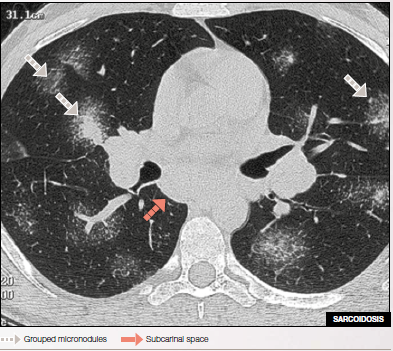

Micronodules with clear outlines & high densities distributed along fissures, peripheral pleura, and intralobular septa.

HRCT shows large sarcoid nodules resembling galaxies associated with enlarged sub carinal lymphnodes.